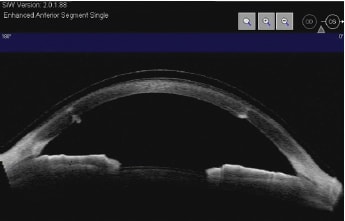

The patient was extremely happy with her lenses and was able to wear them comfortably all day. Fluorescein patterns of the lenses demonstrated central vault, limbal clearance, and no conjunctival blanching or impingement. Visante anterior segment OCT imaging over the lenses showed that the patient had adequate tear exchange beneath the lens, especially over the corneal graft (Figure 9).

Figure 9. Case #3 Visante anterior segment OCT Image over scleral lens demonstrating adequate vault (approximately 70 microns).